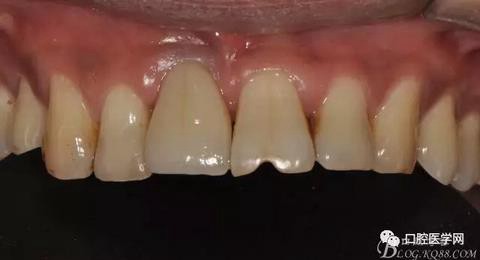

圖21 術(shù)后正位照

圖23 術(shù)后正位咬頜照